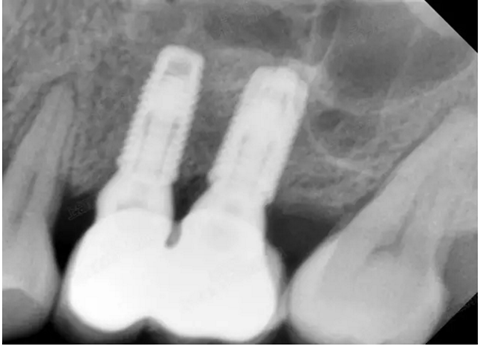

修復(fù)時根尖片

08.png

09.png